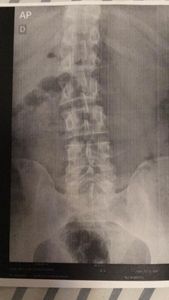

Venho compartilhar brevemente meus desafios de saúde e a importância do seu apoio. Fui diagnosticado com hérnia de disco e compressão do nervo ciático, condições que têm afetado minha qualidade de vida.

Esses problemas causam dores intensas e limitações físicas significativas, impossibilitando-me de trabalhar há quase um ano. Infelizmente, minha situação financeira não permite que eu custeie a fisioterapia necessária para minha recuperação.

Os médicos me recomendaram a fisioterapia como tratamento ideal para fortalecer os músculos do core, consequentemente, reduzir a dor causada pela hérnia de disco que comprime o nervo ciático. Com o apoio financeiro recebido, poderei iniciar as sessões de fisio que trará alívio e permitirá uma maior qualidade de vida.